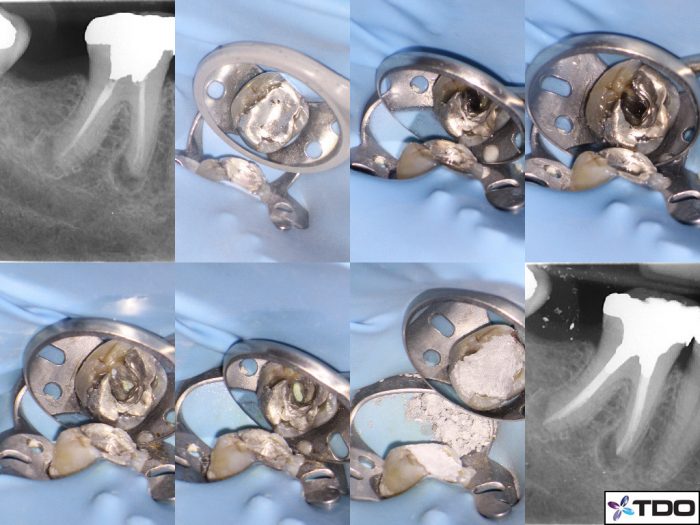

Patient B presented with a previously endodontically treated tooth with persistent chronic apical periodontitis. The tooth had become painful to touch over the last year. Orthograde endodontic retreatment was performed for the tooth over two visits with calcium hydroxide dressing.

At the first visit, the tooth was accessed and old gutta percha remnants removed using retreatment files D1, D2, D3. Stubborn GP in the apical third were addressed with eucalyptus oil and paper points, with the paper point wicking technique. Shaping of the canals was achieved with ProTaper Next instrumentation X2, X3.

Two weeks after debridement was completed Patient B was asymptomatic, and the tooth was obturated with gutta percha and AH Plus sealer.

The previous amalgam restoration was removed and a new amalgam core place utilising 2mm of canal orifice space for retention (aka Nayar core). The patient was then referred back to their general practitioner for the rehabilitation of the tooth with a crown.